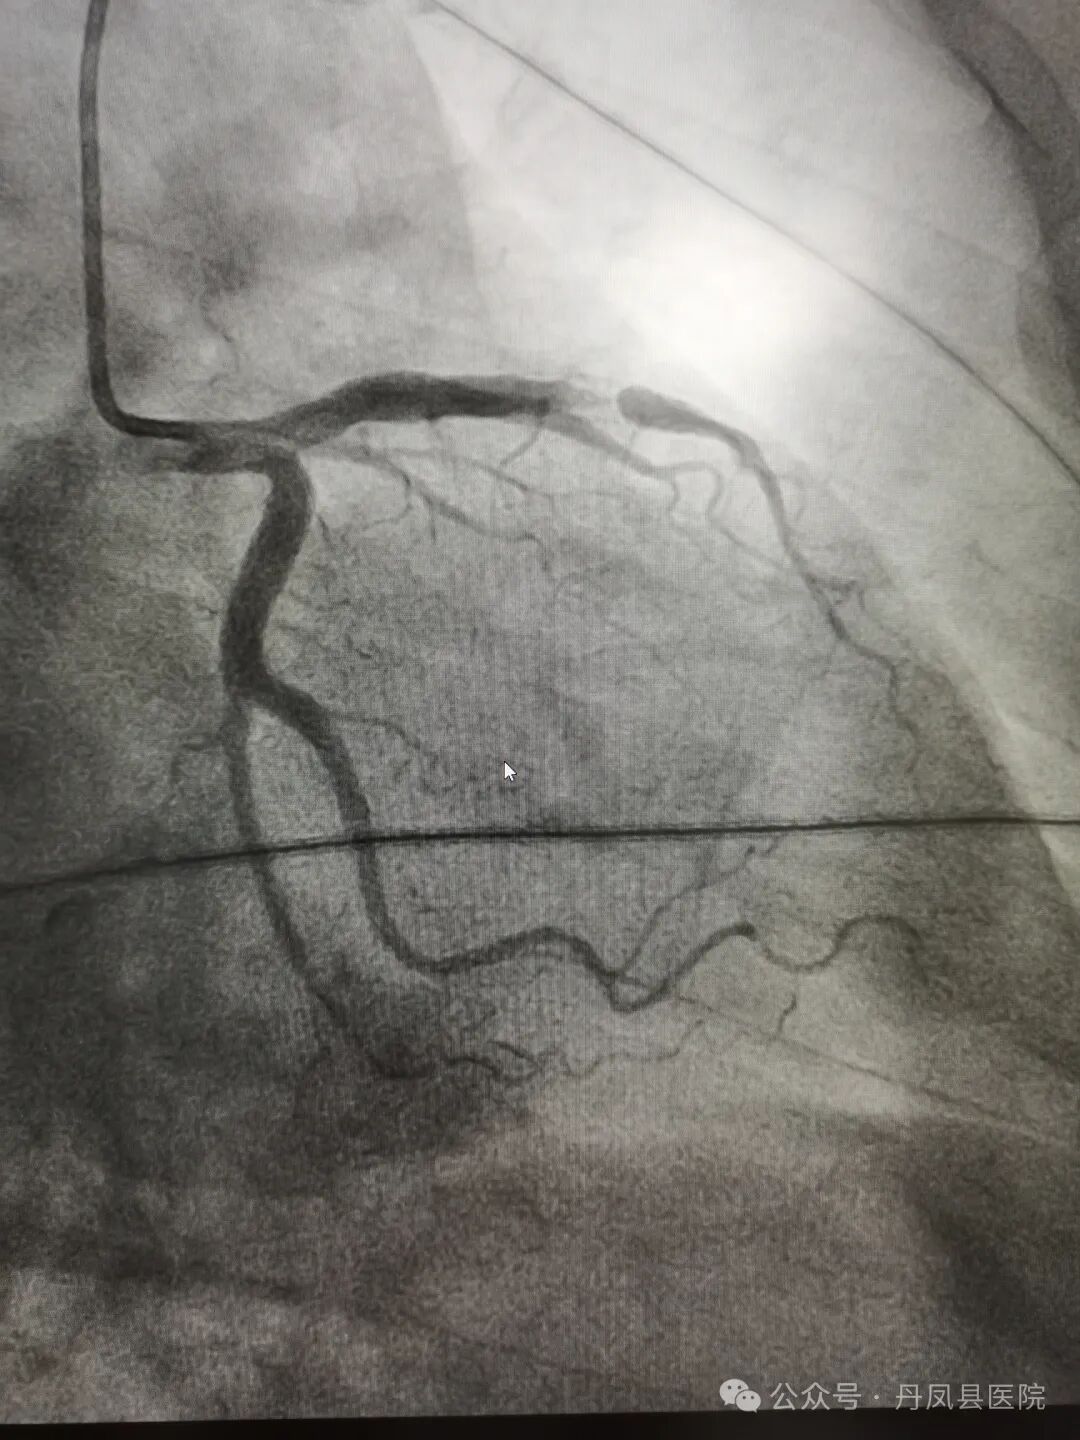

图1、图2为造影下发现病变,图3为术中球囊释放,图4为球囊释放后。